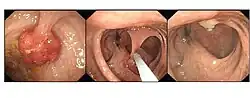

Polyp is identified, snare is passed over stalk and polyp is then removed

Endoscopic polypectomy has been carried out since the early 1970s by both endoscopic snare removal and fulguration of polyps with hot biopsy forceps.[15][16]